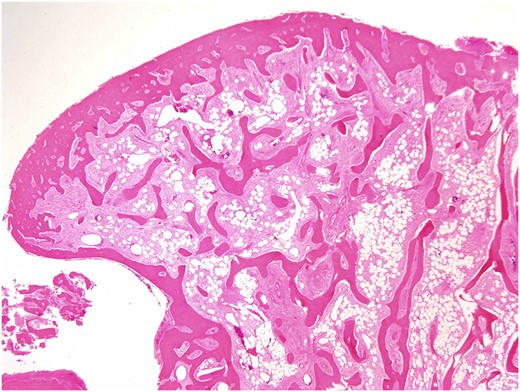

Both specimens showed identical histopathological features, being composed of chronically inflamed nasal mucosa undermined and compressed by sharply demarcated, zonated, multilobulated osseous proliferation without any cartilaginous component. The core and bulk of the lesions was composed of anastomosing, cancellous type bony trabeculae separated by fibrofatty marrow spaces, surfaced by denser cortical type bone, features characteristic of benign osteoma (Figs 2 and 3).

Osteoma, high-magnification photomicrograph. Scanning power photomicrograph showing disrupted pieces of multilobulated variably hyperostotic bone characterized by central anastomosing cancellous trabeculae and fibro-adipocytic interstices, surmounted by more sclerotic cortical type bone. Note the complete absence of any chondroid element (H&E stain, original magnification ×1).

Osteoma, low-magnification photomicrograph. Low-magnification image of a protuberant bosselation emphasizing the bony zonation and total lack of haematopoietic marrow. There is neither significant osteoblastic activity nor appreciable osteoclasis (H&E stain, original magnification ×1.25).